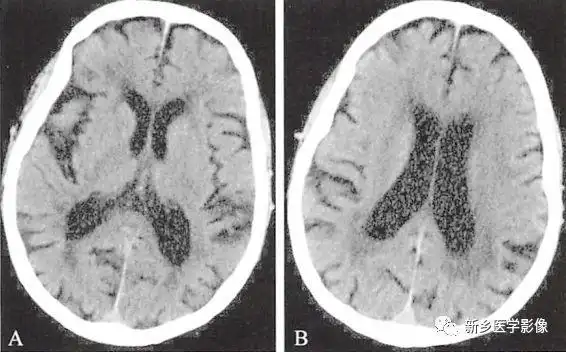

两种常见脑萎缩ct表现

病人女,37岁,间断性头痛史,其他无特殊,既往健康,脑萎缩较明显,需要不